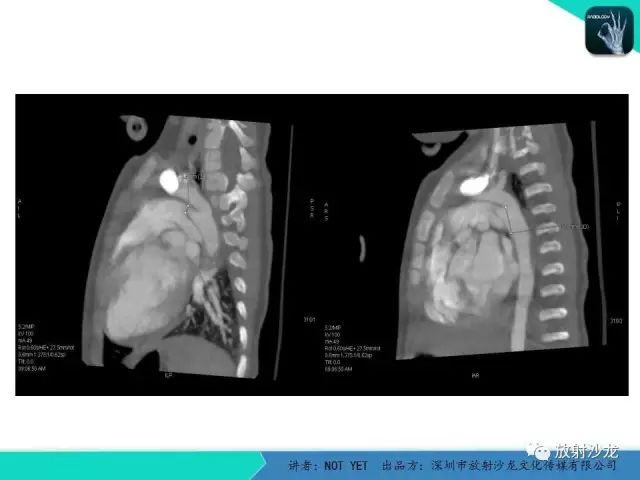

【病例】动脉导管未闭1例CT影像表现